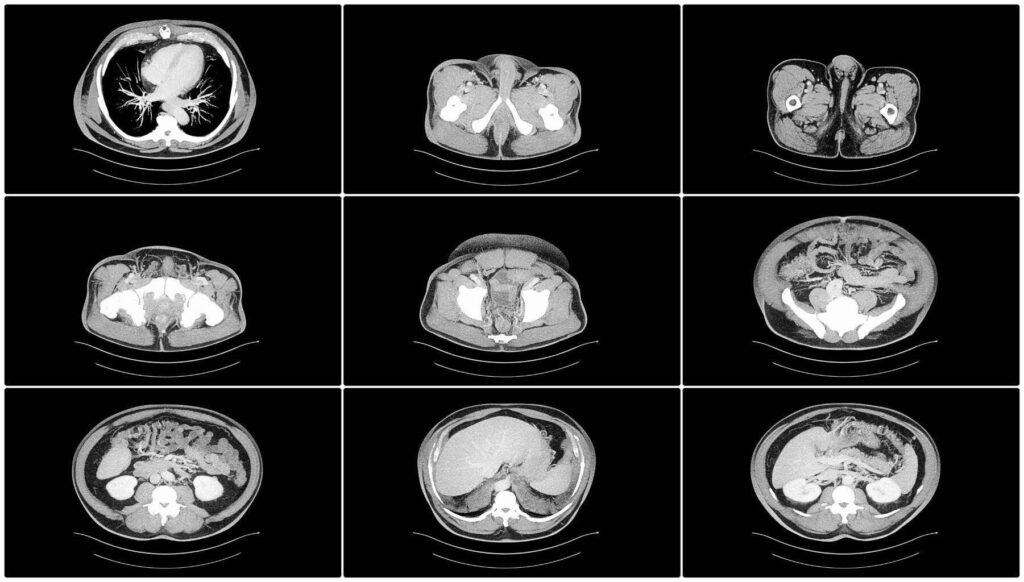

Scannen: Der CT-Scanner verwendet Röntgenstrahlen, um mehrere Bilder des Abdomens aus verschiedenen Winkeln aufzunehmen. Der Scanner dreht sich um den Patienten und nimmt dabei detaillierte Querschnittsbilder des Bauchraums auf.

CT Abdomen Befundung – CT Abdomen welche Organe sieht man?

- Nieren – Befunde: Größe, Form und Lage der Nieren sowie Vorhandensein von Nierensteinen, Tumoren, Zysten, Infektionen oder anderen Nierenanomalien.

- Gallenblase – Befunde: Struktur und Größe der Gallenblase, Vorhandensein von Gallensteinen, Entzündungen (Cholezystitis) oder anderen Anomalien.

- Magen und Därme – Befunde: Darstellung des Magens, des Dünndarms und des Dickdarms (Kolon) auf Anzeichen von Entzündungen, Verstopfungen, Geschwüren oder Wucherungen.

- Nebennieren – Befunde: Nachweis von Nebennierenmassen, Tumoren oder anderen Anomalien.

- Blutgefäße – Befunde: Darstellung der großen Blutgefäße wie der Aorta und ihrer Verzweigungen, Untersuchung auf Aneurysmen, Dissektionen oder andere Gefäßprobleme.

- Lymphknoten – Befunde: Erkennung vergrößerter oder abnormaler Lymphknoten, die auf Infektionen, Entzündungen oder Krebs hinweisen können.

- Muskeln und Weichteile des Abdomens – Befunde: Beurteilung der Muskelstruktur, Vorhandensein von Massen, Hernien oder anderen Weichteilanomalien.

- Peritoneum und Mesenterium – Befunde: Beurteilung der Auskleidung der Bauchhöhle (Peritoneum) und der stützenden Membran (Mesenterium) auf Anzeichen von Entzündungen, Infektionen oder Tumoren.

- Beckenorgane (in einigen Fällen) – Befunde: Untersuchung der Beckenorgane wie Gebärmutter, Eierstöcke und Blase auf Anomalien, Zysten, Tumore oder andere Erkrankungen.